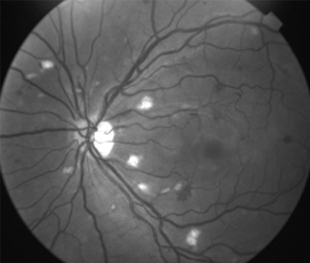

Caso 1

Mujer de 32 años con cefalea después de liposucción con anestesia general 10 días antes de consultar

IDX

Retinopatía de Purtcher Secundaria a Embolismo Graso después de Liposucción

2 meses: disminución de manchas algodonosas y hemorragias con mejoría de circulación

- Bilateral, 20/200 a CD, alteración de la capa de fibras nerviosas, atrofía disco óptico.

- Angiografía: teñido arterial, escape capilar, más tardíamente, no perfusion arteriolar y venular con teñido de las paredes vasculares y dilatación venosa.